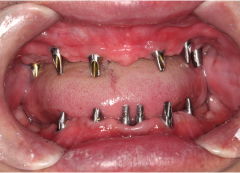

• Tình trạng mất răng:Mất hết răng cả 2 hàm và tiêu xương nặng.

• Phương hướng điều trị:Cấy ghép Implant All On 6 cho cả 2 hàm và phục hình răng sứ cố định.

• Trụ Implant sử dụng:Implant Mis C1 Đức

• Cấy 2 hàm All on 6 Implant Mis C1 Đức